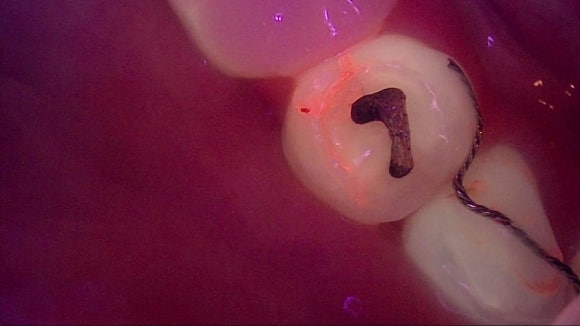

해당 기술은 충치균과 세균의 활성을 수치화 하여

정확한 충치 진단과 크랙 진단에 객관적이고 정확한 자료를 제공해 줍니다.

Q-ray를 이용한 충치 감별

Q-ray를 이용한 Crack 감별

Q-ray를 이용한 충치감별